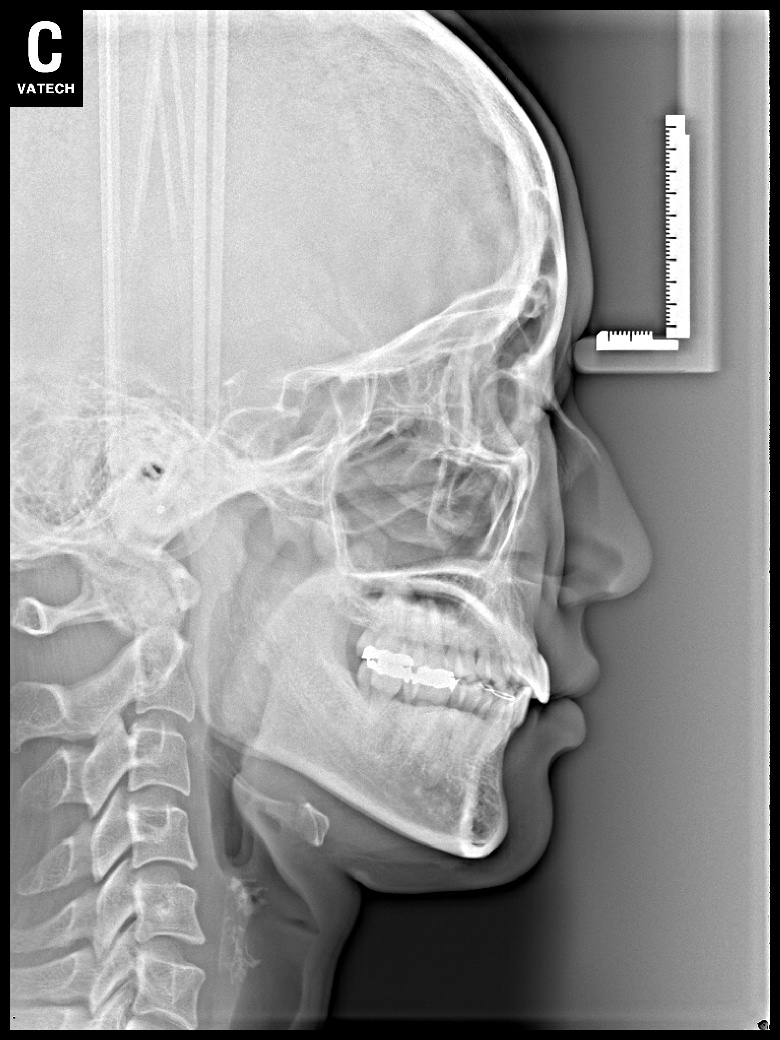

치료 후 사진입니다.